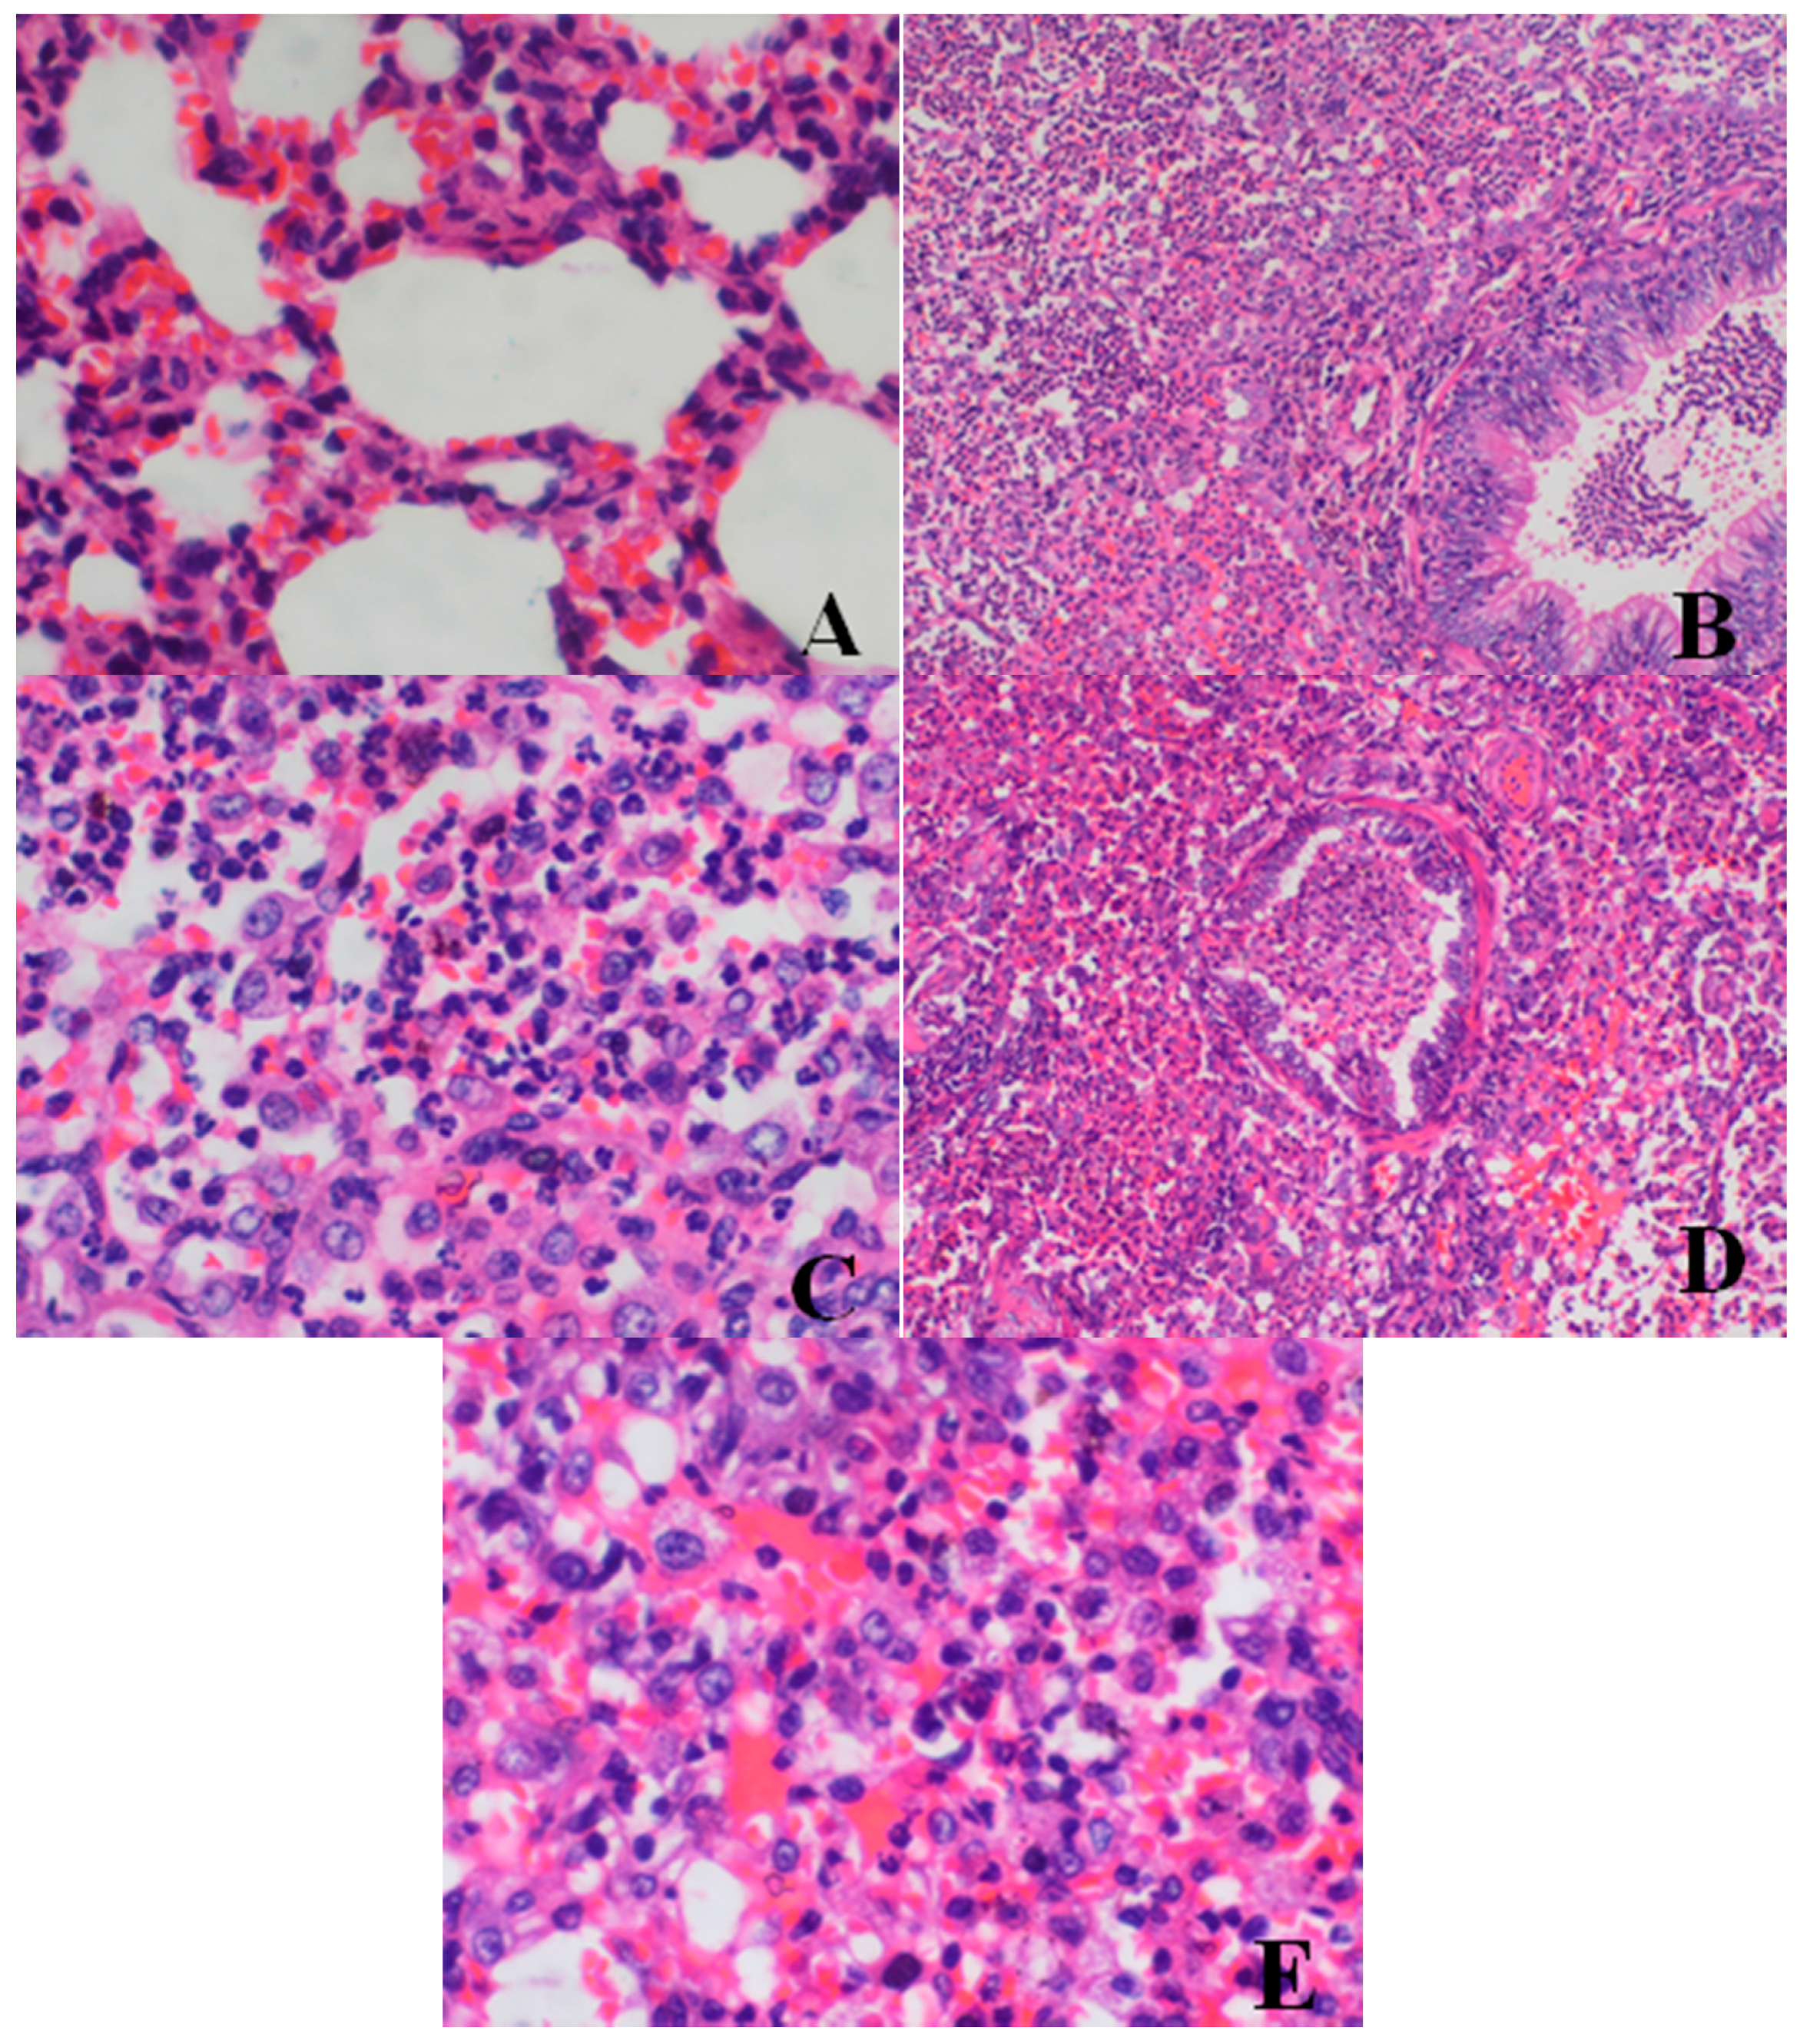

Histopathological Findings

Male reproductive organs (testis, epididymis and prostate)

- Testis: The numbers of seminiferous tubules decreased in dogs belonging to the 80- and 40-mg/kg dose groups, while the tubule lumen decreased and had reduced numbers and types of spermatogenic cells when compared with the control group. Only spermatogonia and some primary and secondary spermatocytes were observed, and there were no mature sperm compared with the control group.

- Epididymis: When compared with the control group, there was a notable lack of mature sperm cells and secretions in the epididymal lumen, as well as a decrease in epididymis lumen size, an irregular shape of the epididymal lumen and an increase in the connective tissue in the interstitium observed in dogs in the 80- and 40-mg/kg dose groups.

- Prostate: When compared with the control group, a reduction in the numbers and size, a thinner epithelium, narrower glandular cavity and increase in the connective tissue in the interstitium were observed in the prostatic acini of dogs in the 80- and 40-mg/kg dose groups.

| Organ | Findings | Dose (mg/kg/day) | ||||

|---|---|---|---|---|---|---|

| 0 | 5 | 20 | 40 | 80 | ||

| Lung | large confluent bronchopneumonia | 0/4 | 0/4 | 0/4 | 2/4 | 2/4 |

| Bone marrow of sternum | decrease in hematopoietic cell numbers | 0/4 | 0/4 | 0/4 | 2/4 | 3/4 |

| Testis | Reduction in numbers and types of spermatogenic cells | 0/2 | 0/2 | 0/2 | 2/2 | 2/2 |

| Epididymis | lack of mature sperm and secretions in the epididymal lumen as well as decrease of epididymal lumen size | 0/2 | 0/2 | 0/2 | 2/2 | 2/2 |

| Prostate | reduction in numbers and size, thinner epithelium, narrowing of the glandular cavity of prostatic acini | 0/2 | 0/2 | 0/2 | 2/2 | 2/2 |